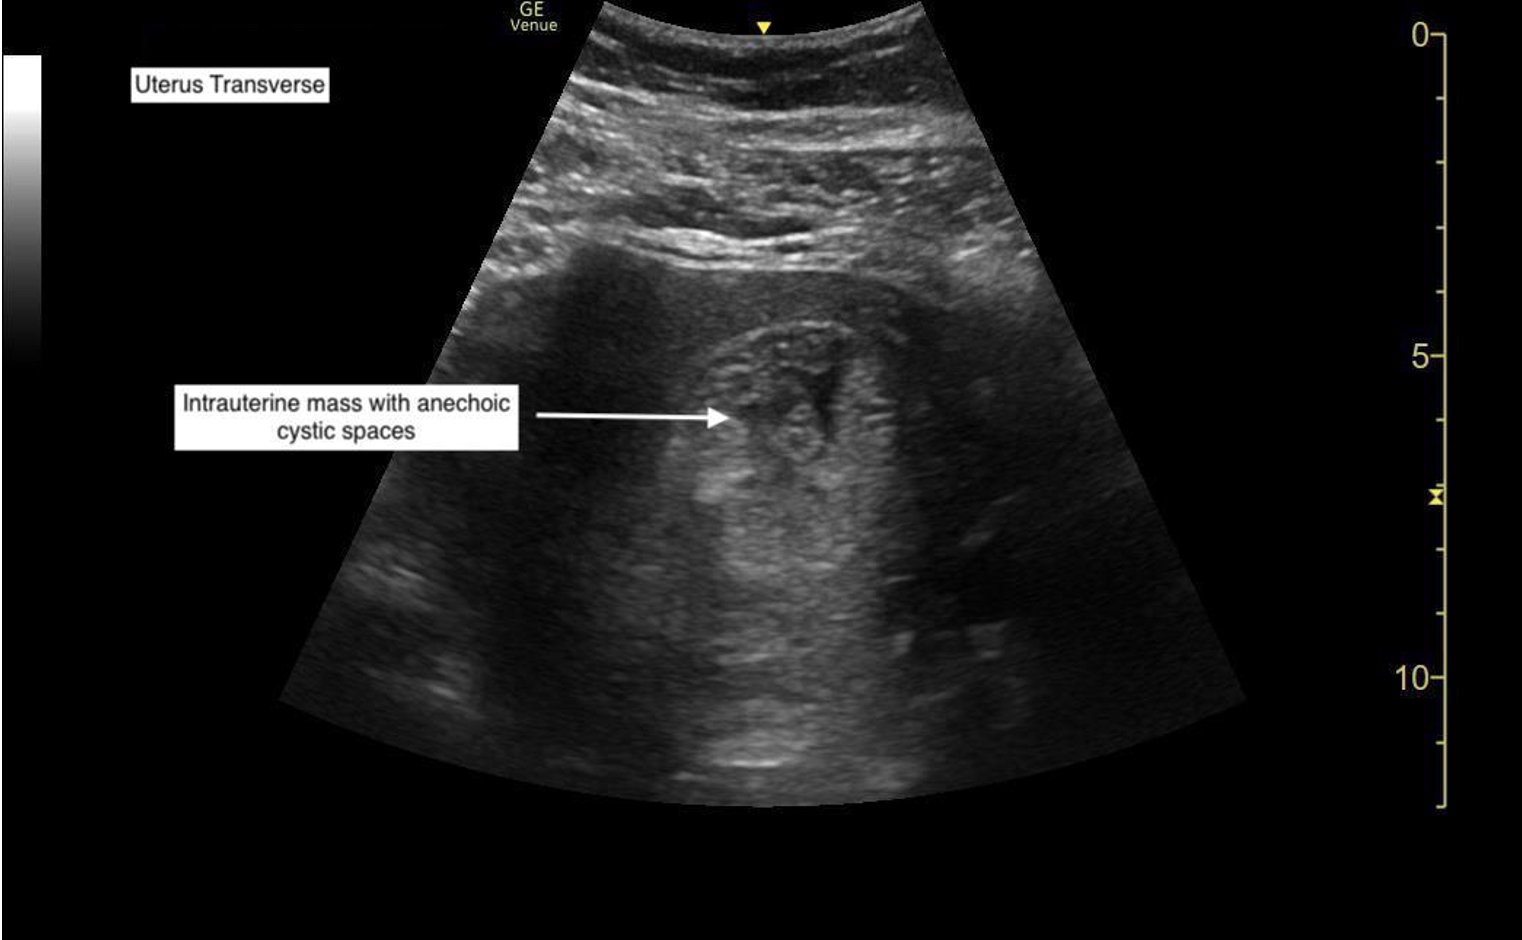

Molar pregnancies are rare complications that can have potentially devastating effects, including neoplastic disease. Given the potential for malignant conversion, proper diagnosis of molar pregnancy is crucial. This case demonstrates the utility of point-of-care ultrasound (POCUS) for molar pregnancy in the emergency department (ED). The patient was a 43-year-old G8P1, 8-week-pregnant female who presented to the emergency department for evaluation of abdominal pain. Her physical exam was notable for abdominal tenderness and a normal pelvic exam. Evaluation included basic labs with a quantitative serum beta human chorionic gonadotropin (βhCG), urinalysis, and vaginal wet mount. Her results were unremarkable with the exception of elevated βhCG to 83,000 mIU/mL. A transabdominal POCUS was performed which showed a heterogeneous mass with several anechoic areas, concerning for a molar pregnancy. Patient was seen by obstetrics and gynecology (OB-GYN) and a transvaginal ultrasound showed similar findings. Dilation and evacuation were performed approximately 5 hours after initial diagnosis on POCUS. Use of POCUS was crucial for expedient diagnosis and appropriate treatment in this patient, highlighting the utility of POCUS for pregnant patients in the ED.